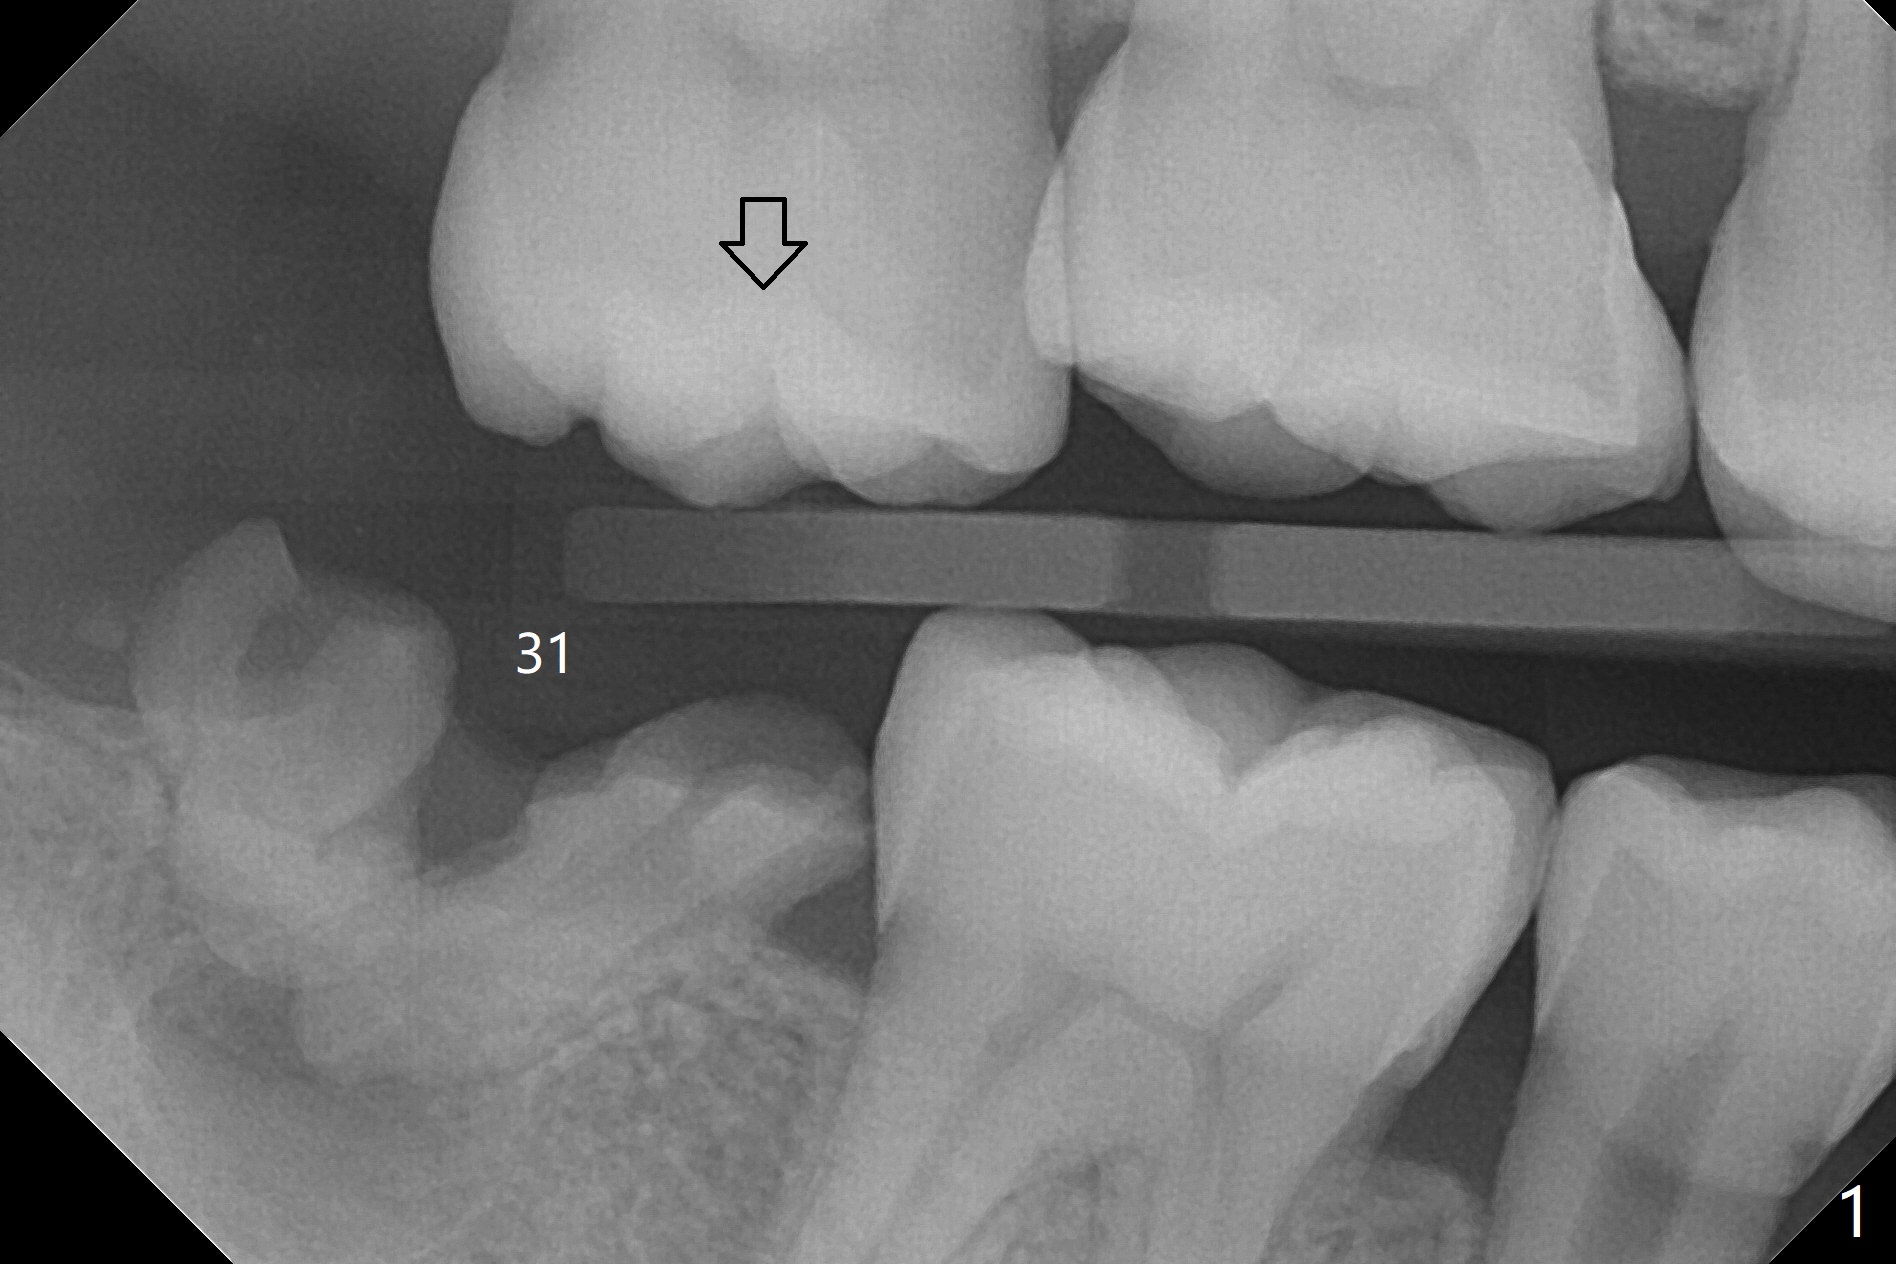

A 39-year-old man finishes orthodontic treatment without intrusion of the upper 2nd molar (Fig.1). He is reluctant for mini-implant placement for intrusion. After extraction of the tooth #31 with periapical radiolucency (Fig.2 *), a 5x11(4) mm Magicore will be placed with guide (Fig.3). Following osteointegration (Fig.4), a burn out core is going to be placed (Fig.5 brown, inside metal, outside plastic). With proper height adjustment, a provisional is fabricated around the core with acrylic (Fig.6 white). If the provisional keeps breaking down under occlusion, the case will be sent to lab for a screw retained crown with unfinished rough occlusal surface so that a thin layer restoration material able to be laid chair-side (acrylic or suction down material). Over time, the opposing tooth will be intruded (Fig.7 arrow).